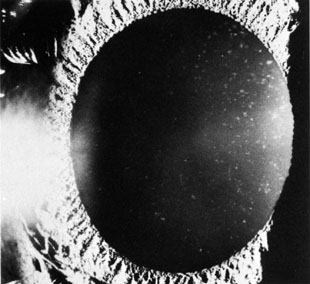

In the exfoliation syndrome (pseudoexfoliation), fibrillar material is scattered throughout the anterior chamber of the eye. Histochemically the material is similar to amyloid. It has been found in and on the lens epithelium and capsule, lens zonular fibers, ciliary epithelium, pupillary margin, iris pigment epithelium, iris stroma, iris blood vessels, corneal epithelium, and subconjunctival tissue (Fig. 7).50,51 On the anterior lens capsule, a peripheral zone of exfoliative material is separated from a central zone by a clear area, presumably from the iris rubbing away the material. The source of the material is not yet known, but it appears unlikely that the lens is the sole source of the particles as deposits of material persist after cataract extraction. It is assumed that multiple sources contribute as part of a generalized basement membrane disorder. Exfoliation syndrome is a systemic disease, as fibrillar material has been found in connective tissue portions of various visceral organs.52 This syndrome is most commonly found in elderly patients.

Fig. 7. Arrows indicate edges of peripheral zone of exfoliation material.